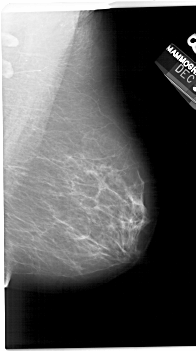

A_1245_1.RIGHT_MLO

RIGHT_MLO LINES 6661 PIXELS_PER_LINE 3706 BITS_PER_PIXEL 12 RESOLUTION 43.5 NON_OVERLAY